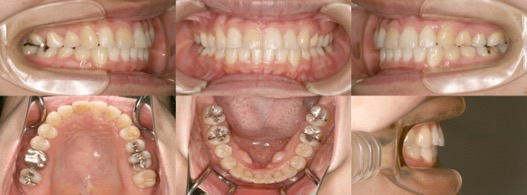

為您介紹隱適美矯正的治療案例。

※案例圖片著作權:隱適美醫師網(禁止轉載)

從案例照片的矯正前後對比中,可以清楚地看出其效果。